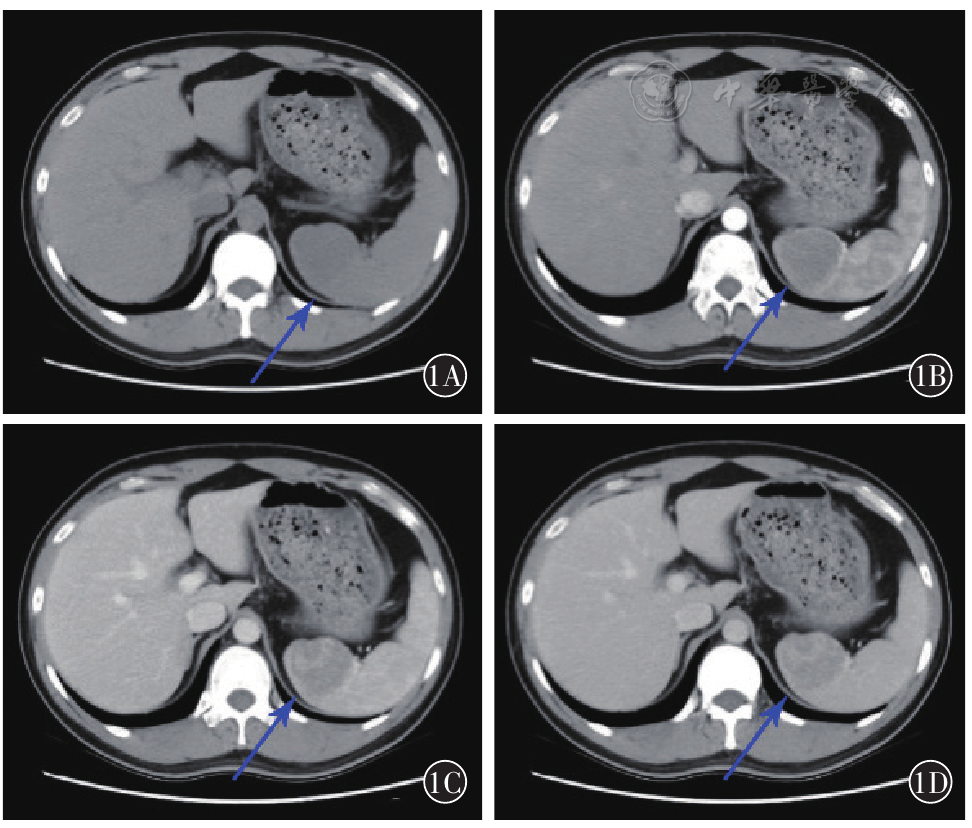

图1 SSANT在CT影像学表现注:1A为轴位平扫示脾脏上极边缘部见大小约4.5cm×4.2cm稍低密度病灶,密度尚均匀,病灶内无囊变及钙化,边界清晰,病灶局部略突出脾脏轮廓;1B为增强扫描动脉期(25s)显示病灶边缘呈小结节样强化,病灶内见不规则线样强化;1C为静脉期(50s)显示病灶呈持续强化,强化范围进一步扩大填充;1D为延迟(1min)后病灶大部分填充,内仍见稍低密度未完全填充病灶,略低于正常脾实质密度